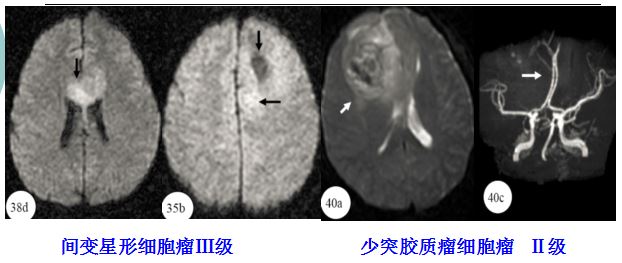

图 DWI与MRA

(1)TDLs的MRI-T2WI往往边界清楚,胶质瘤的MRI-T2WI边界相对模糊。

(2)DWI:TDLs往往急性期、亚急性期较高,逐渐变淡;胶质瘤与PCNSL往往信号越来越高。